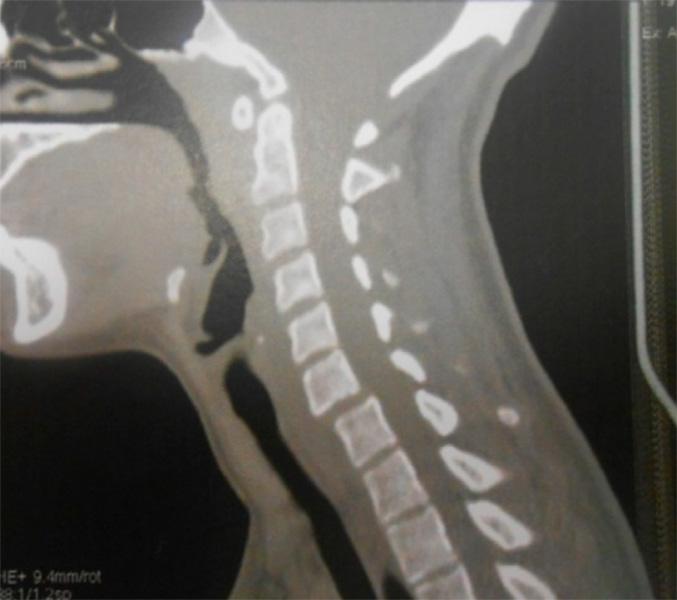

Espondilolisis Cervical

La espondilolisis cervical se define como una hendidura del istmo vertebral o espacio existente entre las faceta superior e inferior de los pilares articulares. Mientras que a nivel lumbar se ha descrito en el 5% o 6%de la población mundial a nivel cervical se considera una anomalía rara, con menos de 100 casos publicados hasta la fecha.